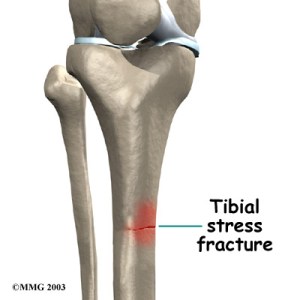

Dejemos la Ilíada y centrémonos en la anatomía propiamente dicha. El tendón de Aquiles está rodeado por una fina capa de tejido conjuntivo o vaina que lo rodea y lo nutre con vasos sanguíneos y nervios y además favorece el deslizamiento del tendón en su movimiento principal que es la flexión plantar. Esa estructura es el paratenon, a su vez existen otras estructuras asociadas derivadas de ésta que son el endo-, epi- y peritenon. Pero no vamos a complicarnos. Pensemos que esa fina capa de tejido conjuntivo es quien sostiene a las potentes fibras de colágeno que forman el tendón dando la nutrición y el apoyo necesario. Esto es muy importante ya que aproximadamente el 80% de las lesiones del tendón se producen en la zona menos vascularizada, que se encuentra entre 2-5 cms de su inserción en el calcáneo.

Las lesiones del Aquiles pueden ser agudas (repentinas ) como la ruptura completa por sobrecarga repentina. Pero también, y mucho más frecuentemente, lo que se producen son múltiples pequeñas microrroturas de las fibras de colágeno a las cuales no damos tiempo a reparar, porque seguimos activos y la molestia no es suficientemente incapacitante. O que se reparan formando cicatrices que se “pegan” al paratendón y que forman calcificaciones y nódulos en su seno. Estamos entonces, hablando de degeneración tendinosa con falta de vascularización del tendón. Muchos pacientes nos cuentan que el dolor mejora cuando llevan un tiempo corriendo o andando. Esto generalmente se debe a un aumento de vascularización (de llegada de sangre) a la zona y por tanto, a un aumento de temperatura que distiende las estructuras y las alivia. Mucha gente lo denomina como “una vez que caliento mejoro algo….”. Pero esto no siempre es así, y cuando se ignora el dolor se forman cicatrices duras que impiden la elasticidad del tendón y al final provocan molestias continuas.

Y ahora sí que podemos empezar a aclarar términos. Cuando hablamos de “tendinitis” hablamos de inflamación del tendón, y si somos muy exquisitos podemos hablar de “paratendinitis” si hablamos solo de inflación del paratendón. No son fáciles de distinguir pues están muy asociadas. Pero esta inflamación puede ser aguda (repentina), por ejemplo tras una gran caminata donde nos sobrepasemos. Pero si nos sobrepasamos más veces de las debidas el tendón posiblemente comience a quejarse progresivamente, porque, como os dije, no le damos tiempo a reparase y readaptarse, estamos cronificando la inflamación por lo que hablamos de “tendinitis crónica” o “tendinosis” y, de nuevo refiriéndonos al paratendón “paratendinosis”. Si la enfermedad progresa podemos incluso observar “nódulos” de tejido fibroso y duro al palpar el tendón, las células inflamadas ya no aparecen porque estamos hablando de un tendón degenerado y rígido, muchas veces calcificado con dificultad para moverse dentro de su vaina. Recordad lo que decíamos antes, también la inserción del tendón y las bolsas serosas pueden lesionarse. Hablamos entonces de “entensitis” o tendinopatía de inserción, y “bursitis” o inflamación de las bolsas serosas. Muchas de estas patologías entran ya dentro del grupo de las talalgias. Por ejemplo, en la enfermedad de Handlung tenemos dolor en la inserción del tendón por prominencia del ángulo pósterosuperior del calcáneo.